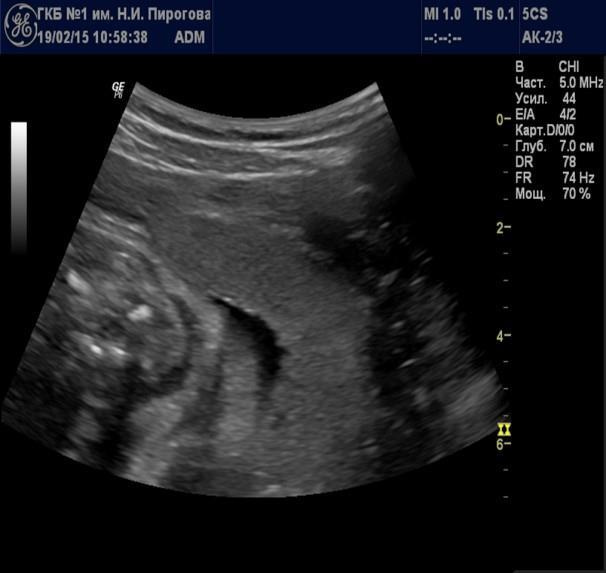

Выявляемые при серошкальном исследовании плаценты ан- или гипоэхогенные зоны чаще всего являются эхографическими срезами участков расширения ее МВП (Рис. 7) и значительно реже сосудов плода (Рис. 8). Расширение МВП может быть связано как с поступлением материнской артериальной крови, и отражать одно из состояний артериального капиллярного русла маточно-плацентарного кровотока (Рис. 9), так и с оттоком в материнское русло венозной крови (Рис. 10). При этом направление тока крови может быть установлено при цветовом допплеровском картировании (ЦДК). Следует иметь в виду, что венозное звено маточно-плацентарного кровообращения состоит из двух функциональных частей: венозных коллекторов плацентарного ложа возле разделительных септ и краевых синусов [10], которые также могут быть расширены (Рис. 11).

Рис. 7. Беременность 33 нед. Участок расширения межворсинкового пространства.